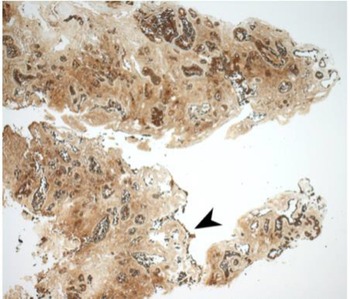

Immunohistochemical staining for pan-cytokeratin AE1/AE3 antibodies demonstrated only very focal residual attenuated surface epithelium (Figure 4). There was strong nuclear and cytoplasmic positivity for S100 immunostain in scattered cells within structures, compatible with Bowman's glands (Figure 5); the same immunostain highlighted small nerve bundles, possibly of trigeminal origin. Immunostaining for angiotensin-converting enzyme 2 (ACE2) receptor showed focal membrane staining in the S100 positive cells in Bowman's glands (Figure 6). There was focal positive staining for synaptophysin, and neurofilament immunostain highlighted small neurites and nerve bundles in lamina propria (Figure 7). No abnormal neural proliferation was identified.

Fig. 4. Immunostain showed possible attenuated residual surface epithelial cells, stained brown (arrowhead). (Pan-cytokeratin immunostain; ×25)